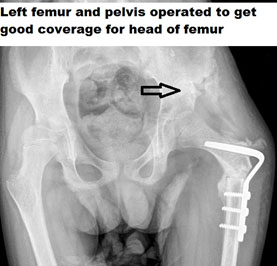

BONY PROCEDURE

A large number of times, CP kids tend to develop bony abnormality due to deforming muscle forces. The kids are born with normal bony architecture, but as they grow old, muscle spasticity causes deformity. The deformity at the hip could be a subluxation, flat foot, or in-toeing and out-toeing at the feet. The assessment of CP is incomplete without an objective evaluation of the muscular and bony deformity. If there are already bony changes that have developed, and if only muscular procedures are done, then they are bound to fail. Bony correction must also be done simultaneously.

Bony procedures in CP could consist of Osteotomies like Varus Derotation Osteotomy of the hip (VDRO) if the head and neck of the femur are vertical. We might need to add a Pelvic Osteotomy to give appropriate coverage for the head of the femur. There could be a need for derotation osteotomy of the leg (tibia) or the thigh bone (femur) to ensure that the child can walk appropriately or in Bedridden kid’s toileting activity is done easily.